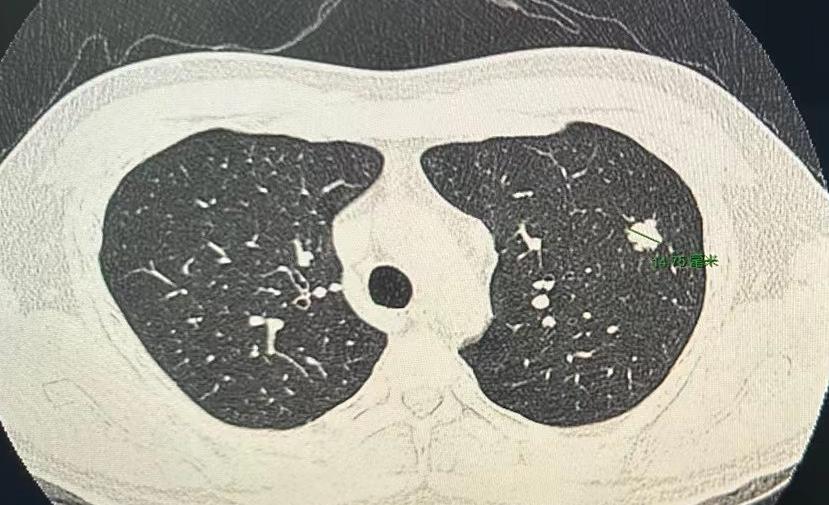

门诊看了五十多位患者,连着做了五台手术,有一台让我心情特别沉重!一位才33岁的小伙子,肺里一个不到1.5cm的结节,却已经是晚期肺癌了...... 患者自述:最近一直头晕、头痛,做了不少检查,最后发现病根在肺上,这个不大的肿瘤,已经转移到了脑部和纵隔淋巴结,先做了脑部手术,昨天又给他做了胸部手术,把肺上的病灶切掉。 手术前见到了他父母,两位老人说,到现在还接受不了这个事实。我也是做父亲的人,看着他们的眼神,能感受到那种无助和绝望。 真的很难想象,一个这么小的肺结节,居然会引起全身多处转移。实在太可惜了,还这么年轻。 但现实就是这样,不会因为谁年轻就手下留情,现在能做的,就是继续往前走!好在医疗技术一直在进步,我们还有办法,还有希望。作为医生,我们会用最好的方案尽力帮他。 这件事也提醒我们,生命真的很脆弱,要好好珍惜身边的人。在疾病面前,家人的陪伴和爱,也是最有力的支撑。[作揖][玫瑰]